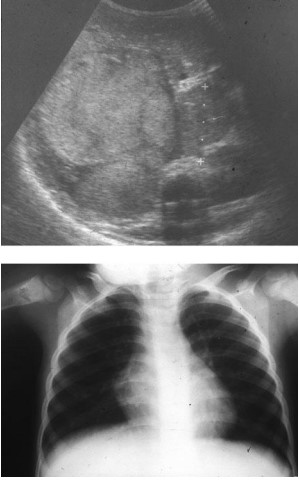

Common abdominal X-ray findings:

Common X-ray Findings: